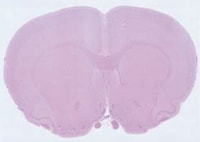

(200×, 이미지 120개 합성)

(150× 비교 이미지)